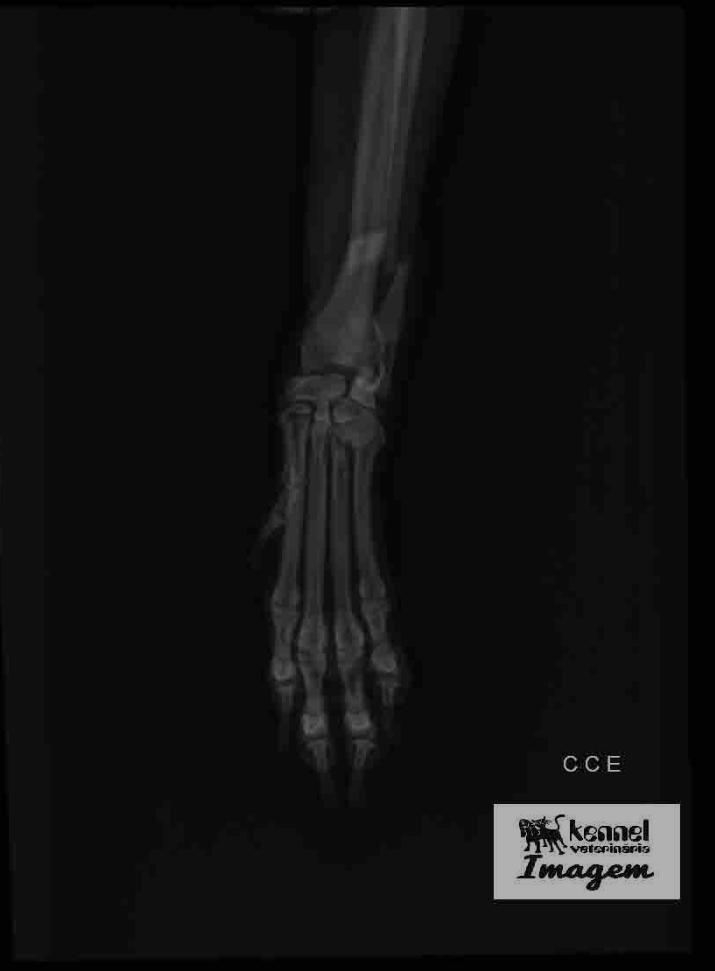

A tutora contou que, logo após o acidente, que aconteceu na quinta-feira (1°), o animal foi atendido por médicos veterinários, que falaram da necessidade da cirurgia. “Ele caiu e quebrou a patinha. Levei na emergência veterinária 24 horas e cobraram R$ 600 para tirar raio-X e colocar uma tala de imobilização. Me orientaram que ele precisaria de uma cirurgia ortopédica, procurei em todos os lugares e só encontrei de dois mil reais para cima”, explicou.